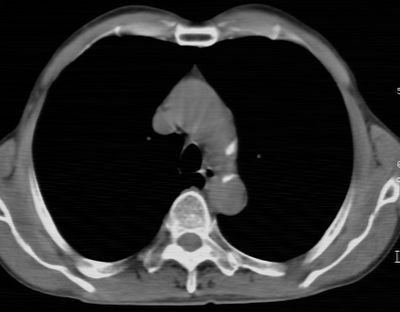

标题: CT24783:m71,既往肺心病史3年,现咳嗽,憋喘。 [打印本页]

标题: CT24783:m71,既往肺心病史3年,现咳嗽,憋喘。

1、左肺上叶spn,毛刺+分叶+血管集束征,考虑周围型肺癌可能性大

2、全小叶性肺气肿。

1)左肺上叶周围型肺癌可能。2)两肺全小叶型肺气肿。

左上周围型肺癌,全小叶型肺气肿。